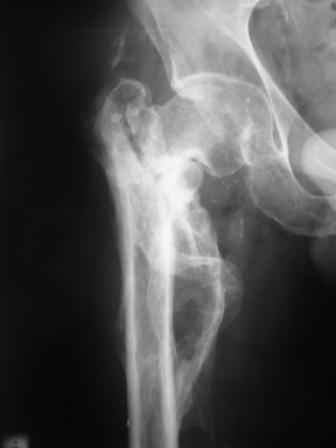

Сросшийся со смещением чрез-подвертельный перелом

Больной Н. 44 года травма 1,5 года назад июнь 2008 года чрез-под вертельный перелом правого бедра. Во время лечения у больного развился алк. делирий, проводилось консервативное лечение перелома.

Беспокоят боли, укорочение конечности. Укорочение 3 см. Ногу поднимает, сгибание ограничено, ротационные движения в полном объеме. На КТ перелом сросся за счет костной мозоли. Что делать?

Протез? Если «да» Можно ли обойтись стандартной ножкой Corail?

Или межвертельная остеотомия?